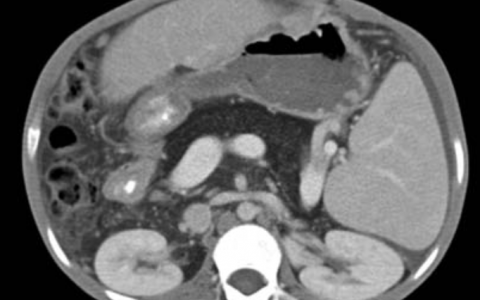

A 26-year-old man who had emigrated from Nepal 7 years earlier was referred to the pulmonology clinic with several months of ankle swelling, a 2-month history of cough and unintentional weight loss, and a 3-day history of leg rash. A chest radiograph showed hilar lymphadenopathy (left). Physical examination was notable for erythematous, tender nodules and plaques on the anterior shins (middle). There was also swelling and tenderness of the ankles. Computed tomography of the chest showed enlarged mediastinal and hilar lymph nodes (right) and normal lung parenchyma. Transbronchial biopsy of the right paratracheal and hilar lymph nodes was performed. Histopathological analysis showed noncaseating granulomas. Microbiological studies for fungal and mycobacterial infections were negative, including a nucleic acid amplification test for Mycobacterium tuberculosis. What is the most likely diagnosis?

一名26岁男性患者,7年前从尼泊尔移民至美国,因数月来踝关节肿胀、2个月咳嗽伴体重不明原因减轻,以及3天前腿部皮疹前来肺科门诊就诊。胸片显示肺门淋巴结肿大(左图)。体格检查发现胫骨前侧有红色、压痛的结节和斑块(中图),同时伴有踝关节肿胀及压痛。胸部CT显示纵隔及肺门淋巴结肿大(右图),肺实质正常。对右气管旁及肺门淋巴结进行了经支气管活检,组织病理学分析显示非干酪样肉芽肿。针对真菌及分枝杆菌感染的微生物学检测均为阴性,包括结核分枝杆菌的核酸扩增试验。最可能的诊断是?